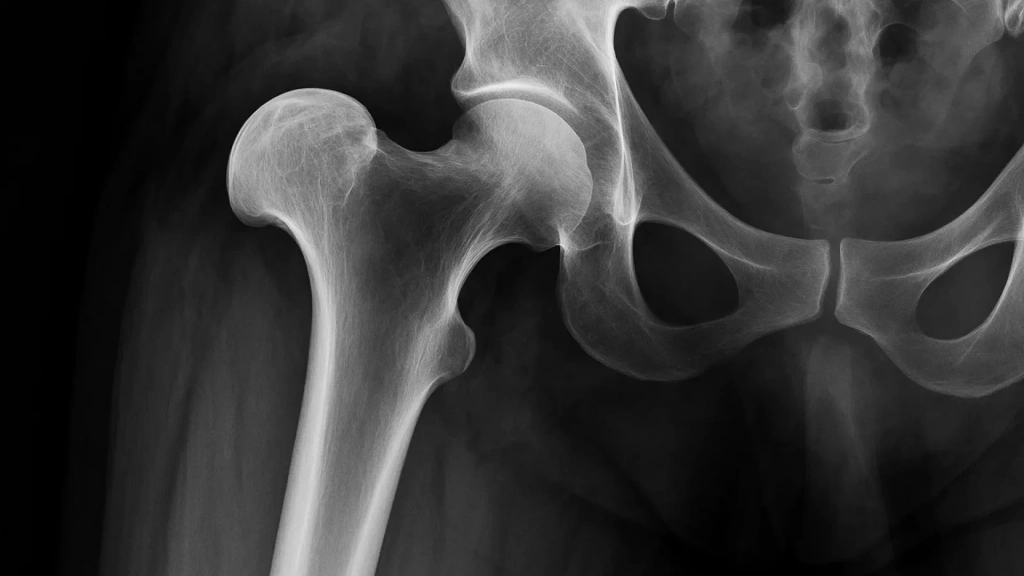

Вывих бедра — это серьезная травма, во время которой головка самой крупной кости нашего тела, бедренной, буквально «выскакивает» из своего естественного места — вертлужной впадины таза. Эта травма не только мгновенно обездвиживает человека, но и несет реальную угрозу повреждения нервов, сосудов и будущего развития артроза.

Тазобедренный сустав — один из самых мощных и стабильных в нашем теле, но и он имеет свои пределы прочности. Вывих бедра — травма специфическая: она никогда не происходит просто так. Для того, чтобы головка бедренной кости выскочила из вертлужной впадины, требуется значительная сила или специальные условия.

Диагностика

Диагностика вывиха бедра начинается с осмотра врача. Для подтверждения диагноза, точного определения типа вывиха и выявления возможных сопутствующих повреждений обязательно проводится рентгенография тазобедренного сустава в двух проекциях. В сложных случаях врач может назначить компьютерную томографию (КТ) или магнитно-резонансную томографию (МРТ).